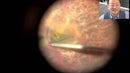

Gripping Forceps with a sandblasted platform, Attached to a Squeeze Handle, with RUMEX Flushing System, 23 Ga